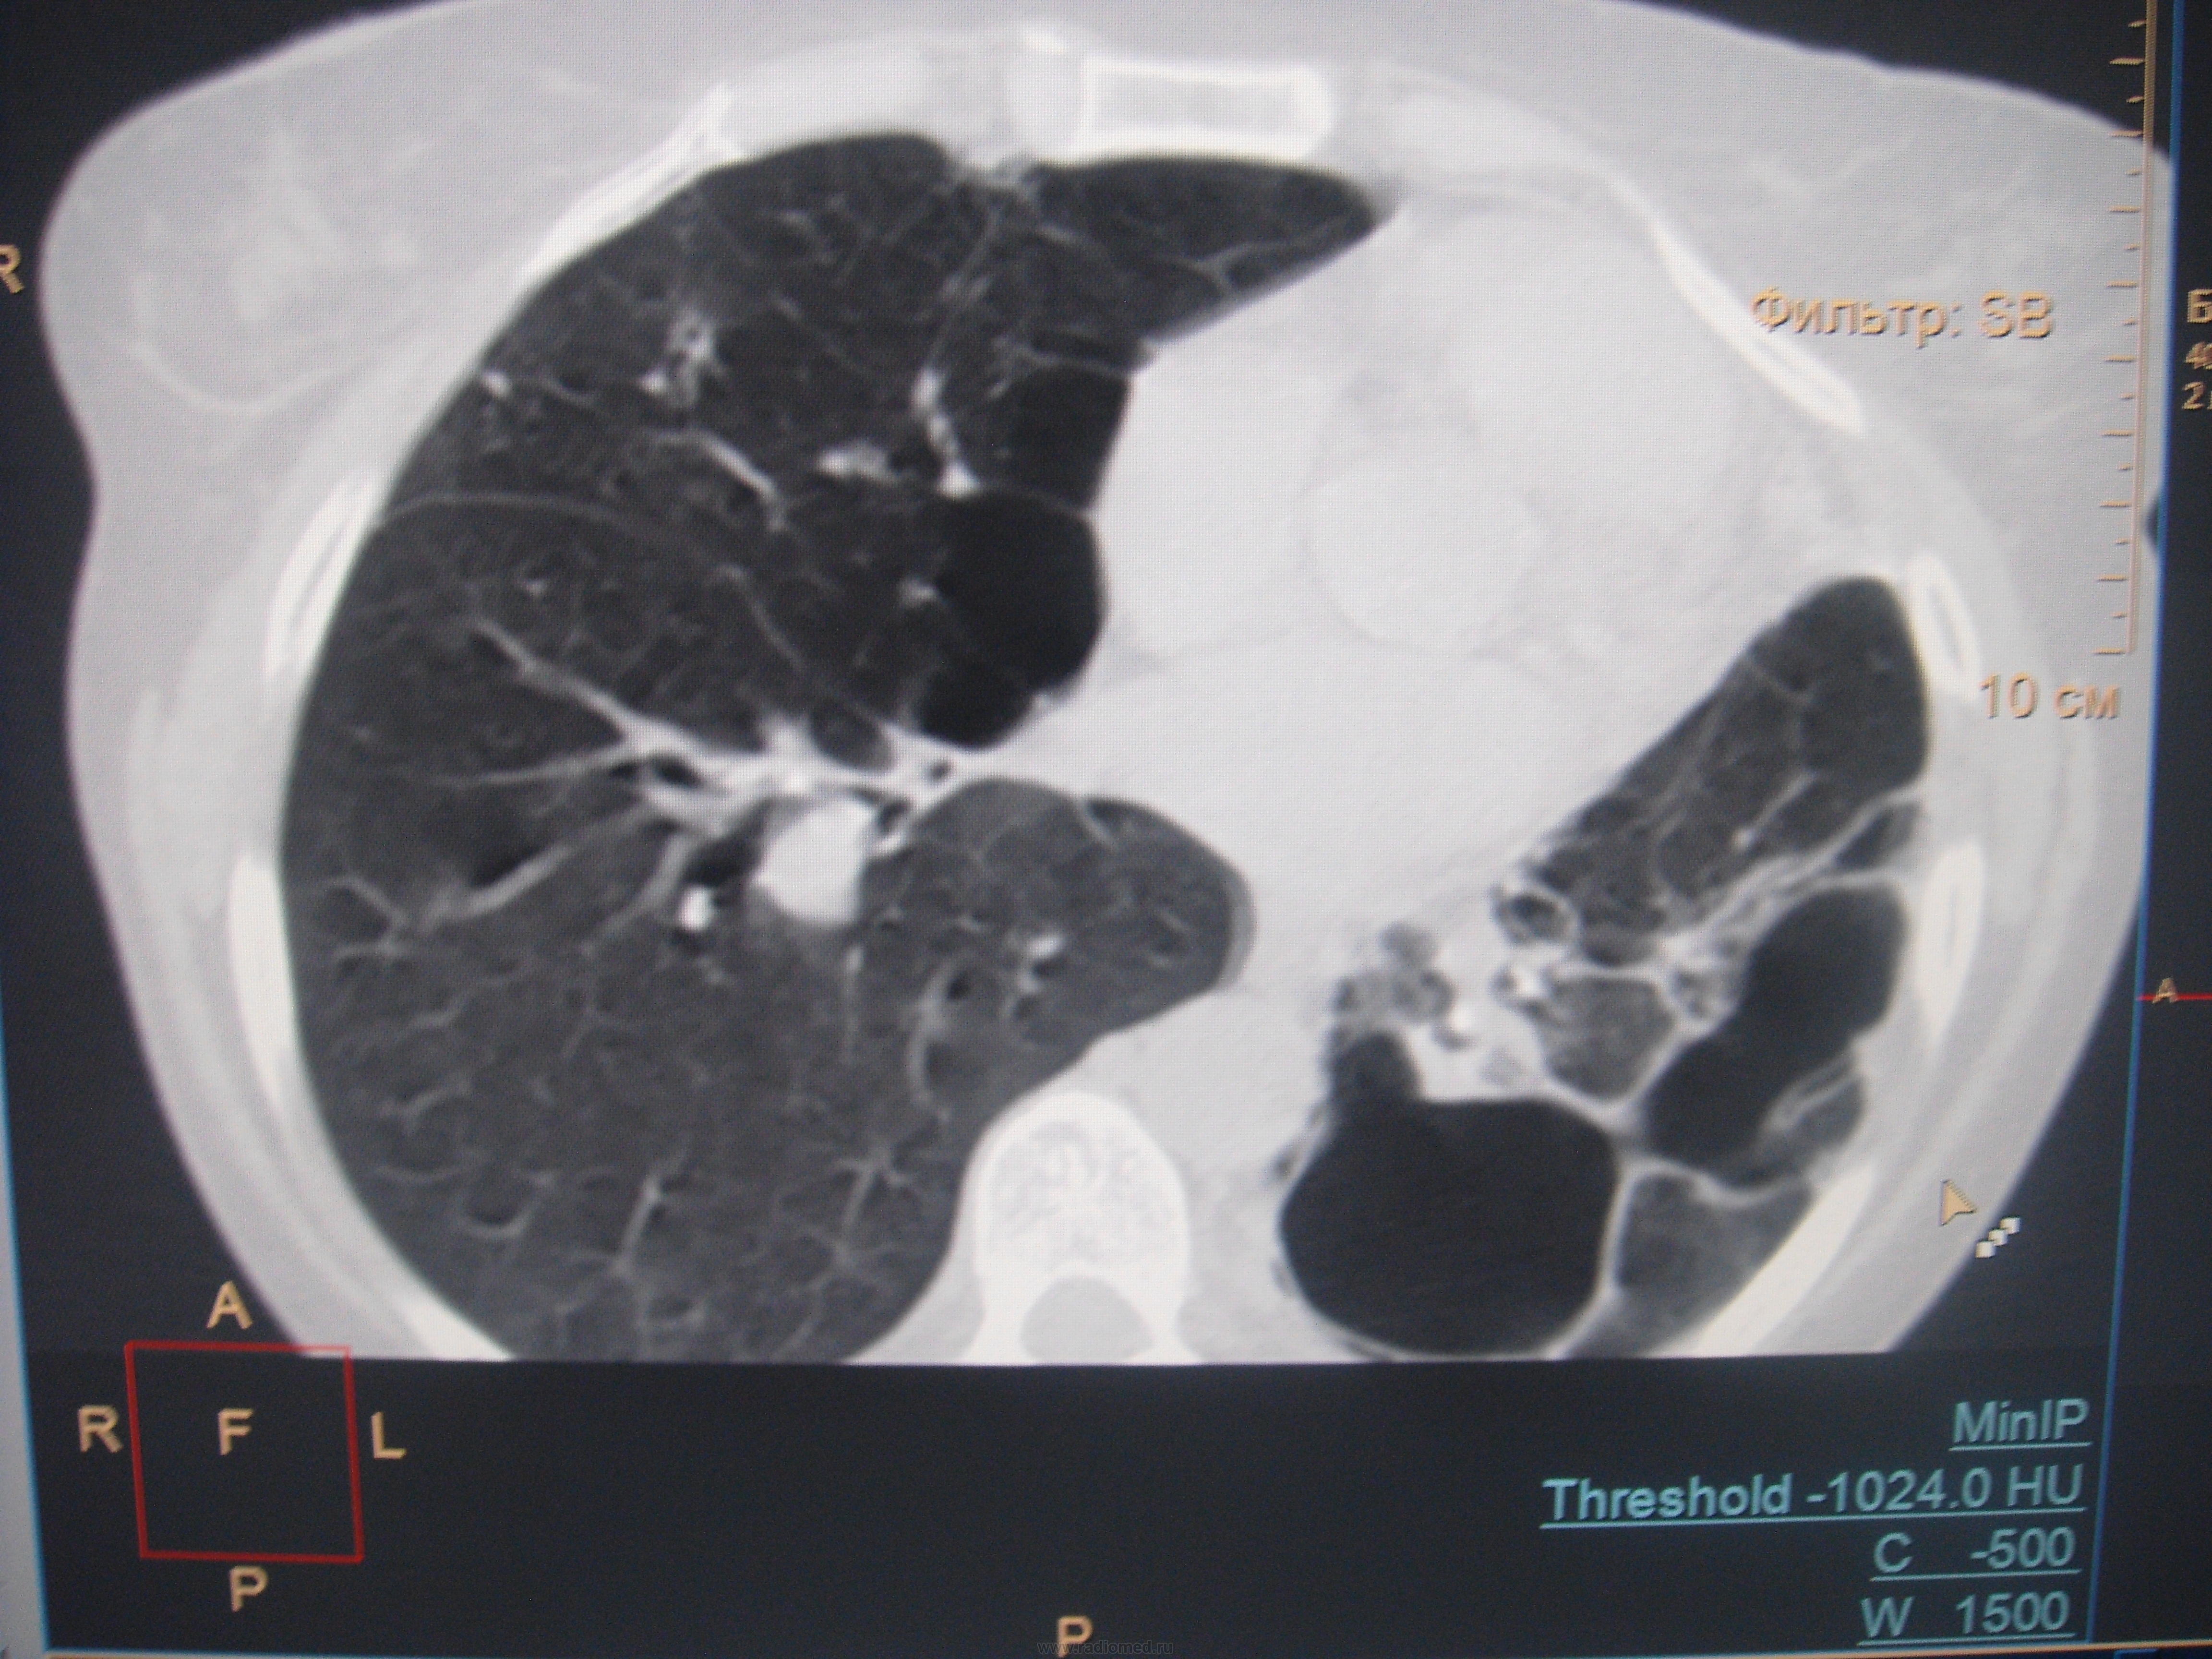

Больная с 03 года выявлена с диагнозом ФКТЛ. Ведет асоциальный о  браз жизни, лечится по настроению. На снимках- одни страсти и таких живучих больных- хроников уже мало. Абацилирована с 06года, если бы высевала, ведя такой образ жизни, давно бы сгинула.

Ну, что ж, ей крупно повезло, что есть запаска в виде еще одного легкого.

Ну да, правое тоже поражено, но не в таком виде.

Да, после пульмонэктомии легче живется наверняка, чем с таким пораженным легким. Удалять нельзя в этом случае- недовес, недоедание, ХСН, ДН и куча до сопут заболеваний-  алкоголизм, глухая, как пробка- от препаратов..

Да, по всей видимости, на обычных рентгенограммах, возможно и томограммах, картинка весьма напоминает фиброзно-кавернозный туберкулёз, который, как трактует фтизиатрия относится к запущенным формам туберкулёза, за который ох как сильно бьют!

Не могу сказать, что видел сильно много ФКТ, но видел..., а представленный случай, на мой взгляд ФКТ не "пахнет". При таких то полостищах, а может быть и кистах слева, довольно интеллигентная картинка справа...

А может быть то не бывшие "каверкоты", а дизонтогенетические кисты?

особенности патологической анатомии туберкулеза, сочетающегося с кистозной гипоплазией легких был изучен выдающимся русским патологоанатомом, антропологом, биологом В.Г.Штефко. 100-летие В.Г.Штефко было отмечено в 1993 году.  В.Г. Штефко считал, что  дегенеративные легкие особенно восприимчивы к туберкулезной инфекции. Мнение В.Л. Катенёва ("а дизонтогенетические кисты?") не фантастика. Вероятность того, что туберкулез легких развился на фоне порочного легкого, очень даже высока. Кроме того, отечественными исследователями подробно описано "разрушенное легкое", как исход прогрессирущих форм туберкулеза.